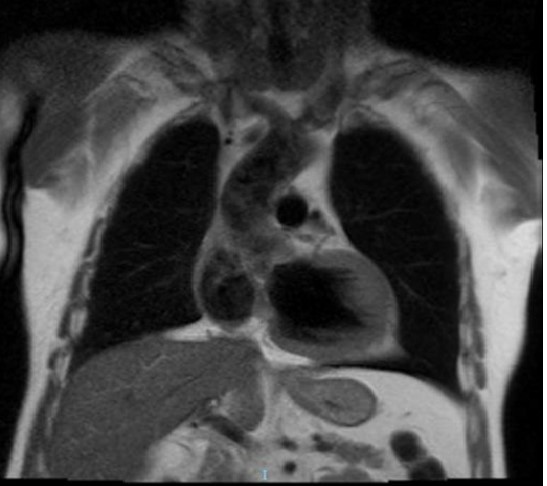

RNM Cardiaca: informa grosor miocárdico NORMAL (máximo 12 mm en segmento anteroseptal basal); tanto en cavidad derecha como en cavidad izquierda se identifican trabéculas paraseptales prominentes. Resto de parámetros dentro de la normalidad